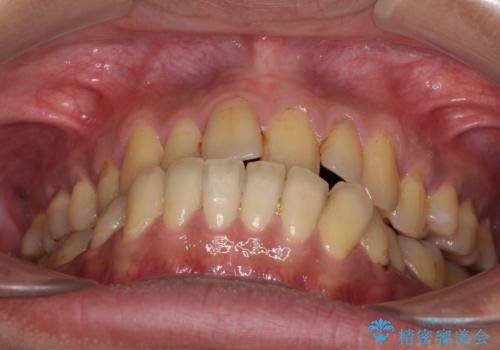

前歯のクロスバイトを改善 ワイヤー装置での非抜歯矯正

- 30代男性

- 骨格的な咬み合わせのズレ、前歯のデコボコとクロスバイトを気にして来院された患者様です。

骨格のズレが顕著であると診断され、マウスピース矯正では奥歯の咬み合わせが整えにくいと判断し、ワイヤー装置による矯正治療を行うこととしました。

上下の叢生は速やかに改善できましたが、右側のクロスバイトの改善に1年以上の期間を要しました。